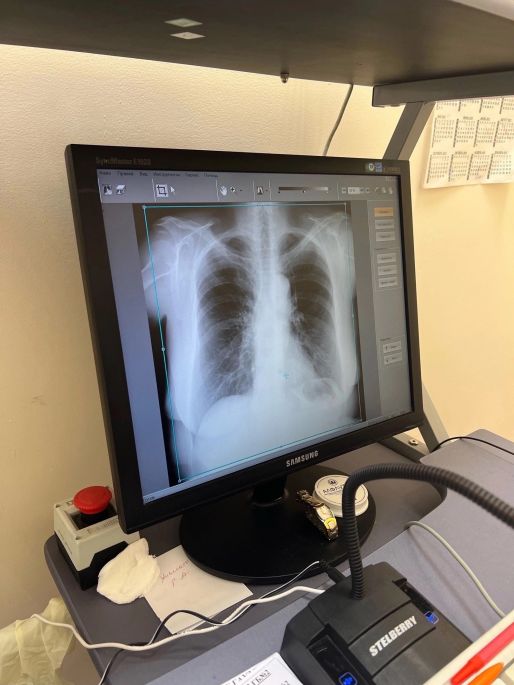

Рентгенологическое отделение оснащено современным оборудованием. В пресс-службе Минздрава рассказали о работе специалистов.

В Минздраве Челябинской области рассказали о работе врачей-рентгенологов магнитогорской горбольницы № 2. Само отделение состоит из двух кабинетов флюорографии, двух рентгеновских кабинетов и пяти кабинетов ультразвуковой диагностики. Также работает кабинет маммографии и томографии. Специалисты проводят исследования при помощи современного оборудования.

В кабинетах флюорографии установлены цифровые малодозовые флюорографы, а в рентгенкабинетах — диагностические рентгеновские комплексы «Медикс-Р-Амико» и телеуправляемый «Протон». Помимо стационарных комплексов врачи используют и портативное оборудование: передвижные рентгеновский и ультразвуковой аппараты. В 2021 году в отделение поступил японский компьютерный томограф, аппарат приобрел Минздрав Челябинской области.

Ежегодно специалисты магнитогорской горбольницы № 2 проводят около 50 тысяч флюорографических исследований, а также около 12 000 — 13 000 рентгеновских исследований и не менее 20 тысяч ультразвуковых исследований.